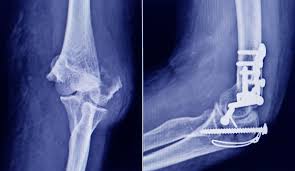

El material ensayado puede presentar dos tipos de rotura Fractura dúctil. Cuando se produce este tipo de fractura los pacientes generalmente requieren una férula durante la primera semana de recuperación a medida que la inflamación disminuye en la muñeca.